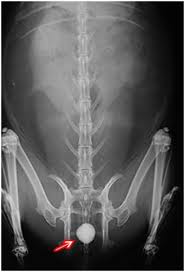

Cystic Calculi

(Bladder Stones)

•Clinical Signs:

Frequent urination, straining to urinate

Blood in the urine.

•Treatment: Surgical Removal

•Prevention: Less pellets, more fiber in the diet.